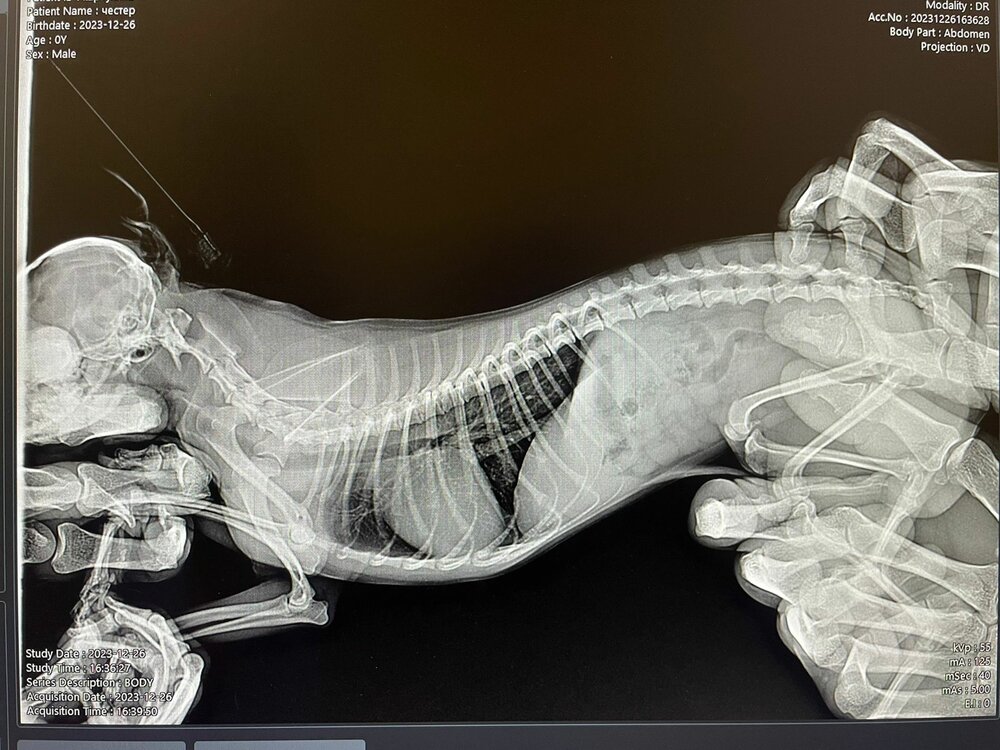

Ребята помогите, у кого был такой диагноз. Собака болеет уже вторую неделю. Врачи ставили разные диагнозы. Лечили нам и уши и живот, пока не доехали в другой город. Диагноз дискоратия грудного отдела. Назначили уколы флексопрофен. Сегодня последний укол, делаем их на ночь. Под утро начинает скулить. Уже и не знаем что делать. Может кто сталкивался, как лечили?

• 1_IMG-20231226-WA0042.jpg

Чихуахуа (IMG-20231226-WA0042.jpg)

142,6 KB · Просмотры: 159